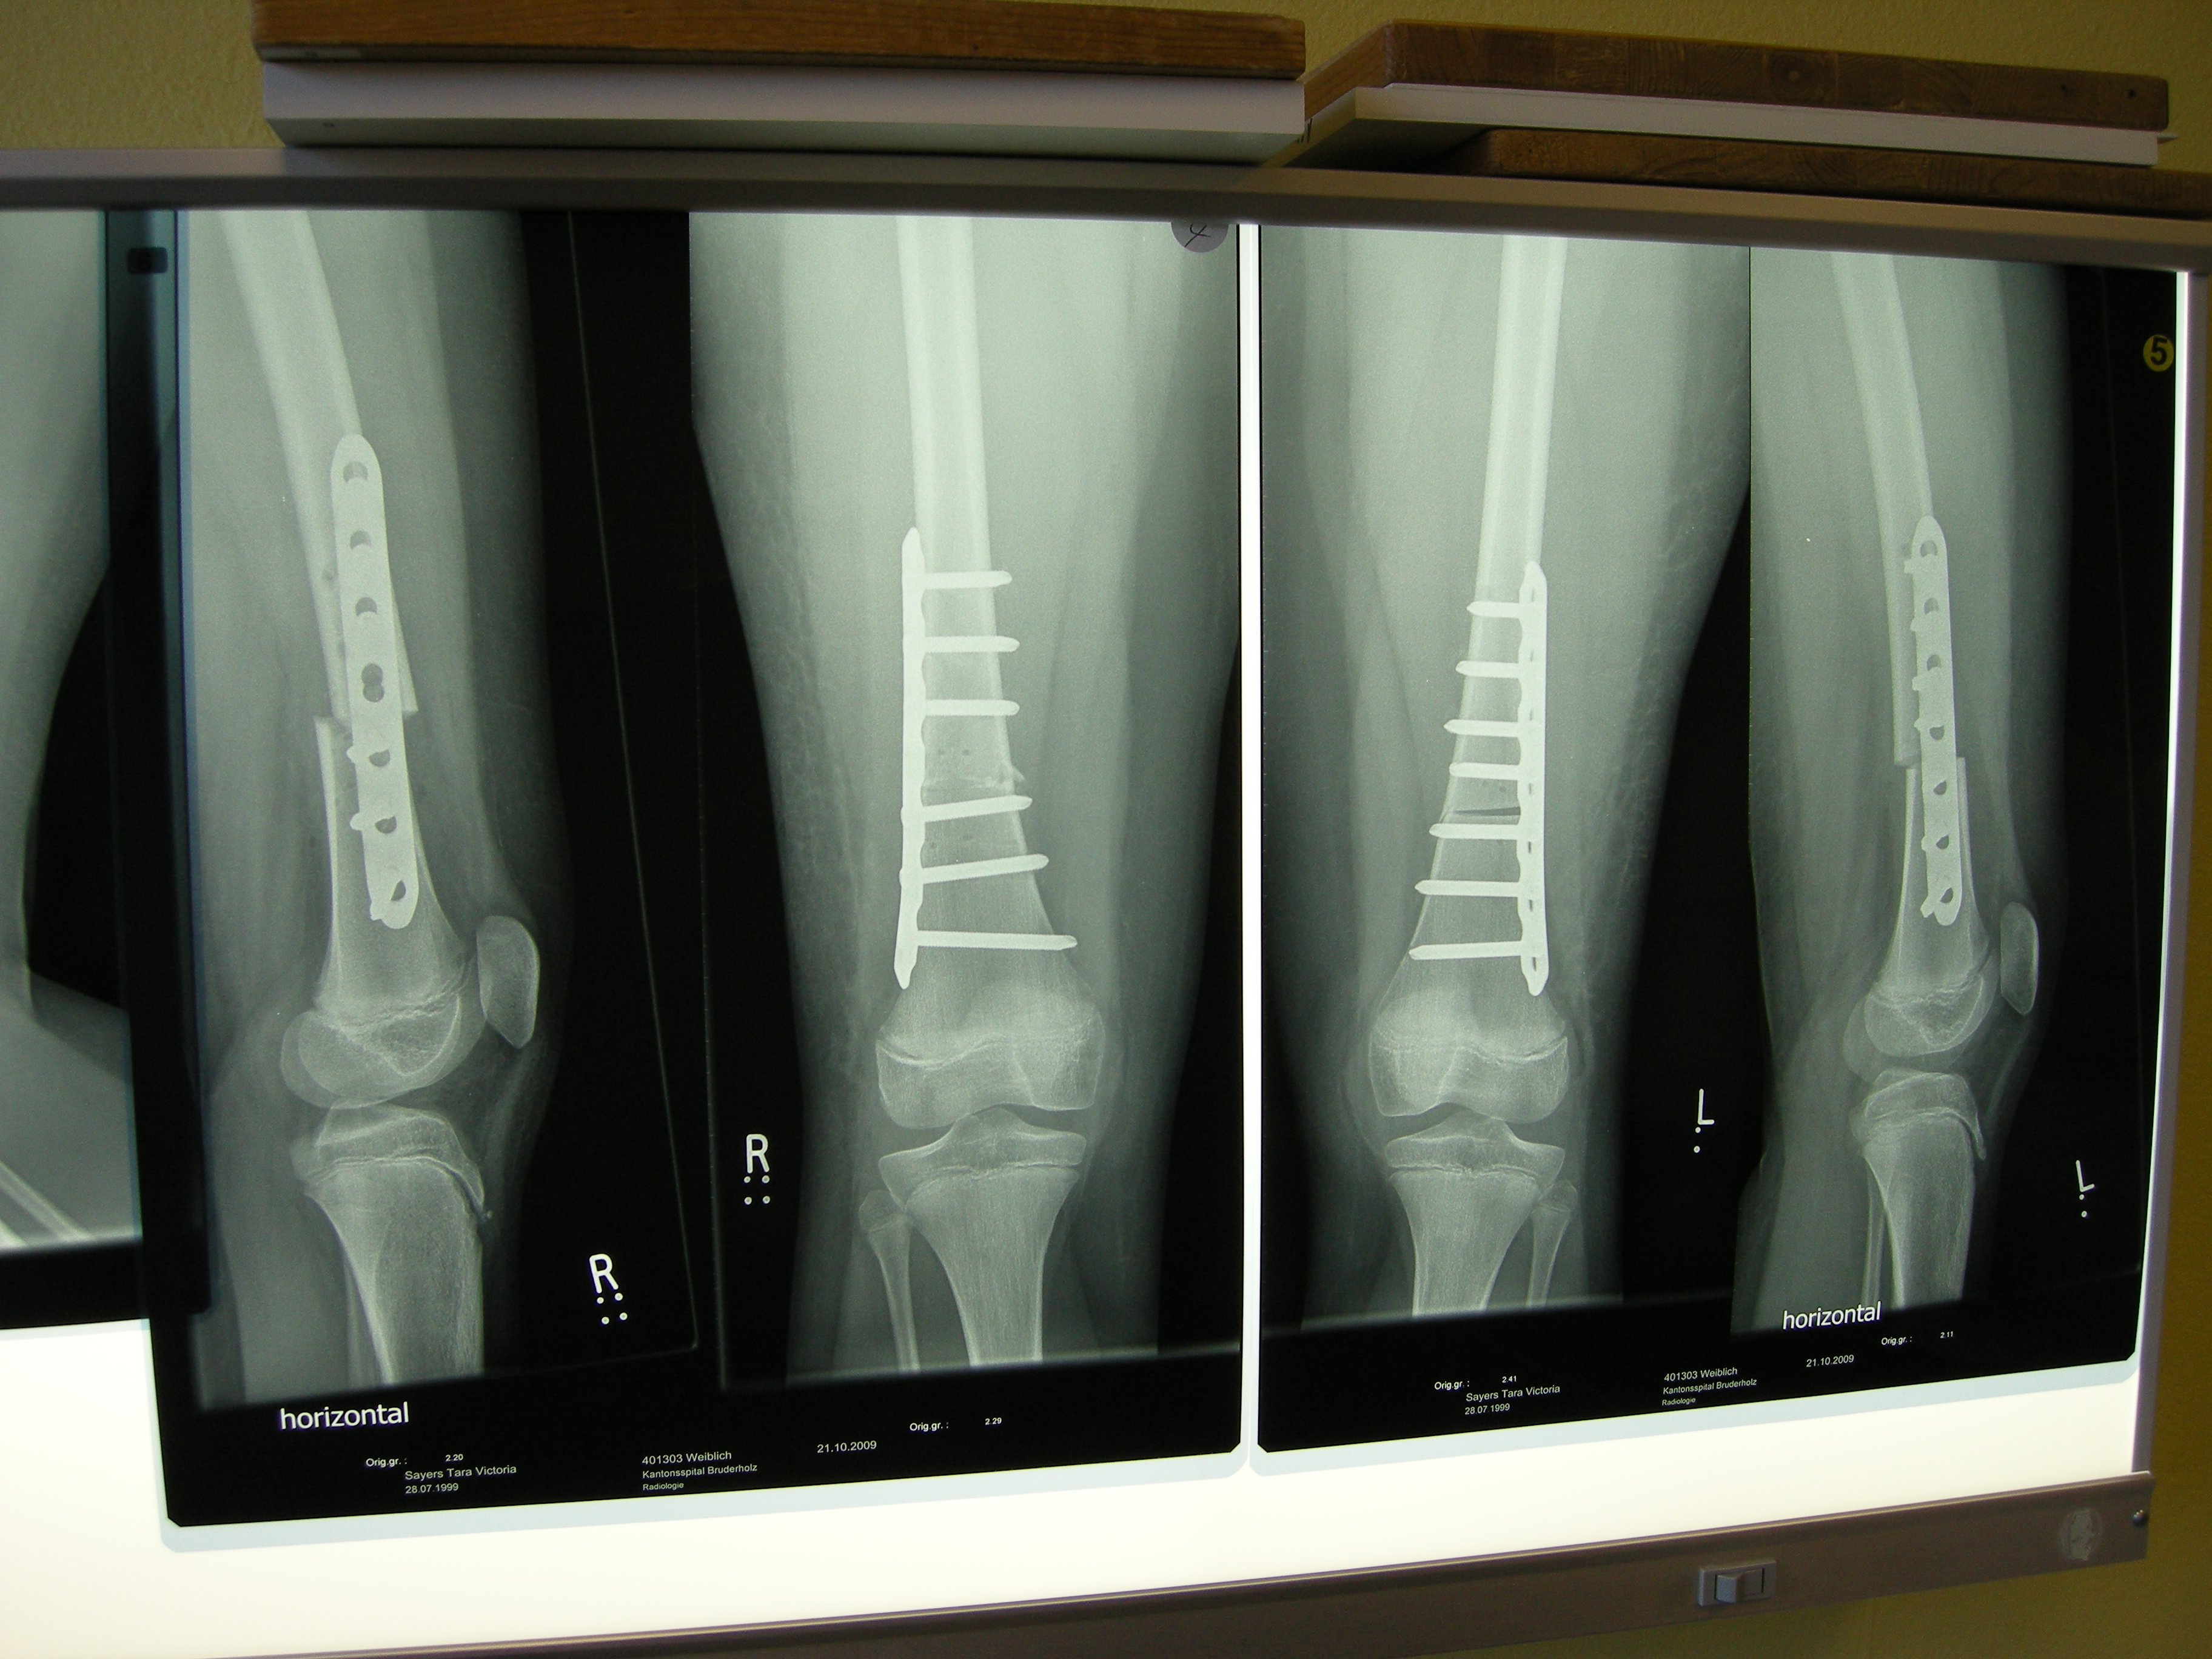

XRays